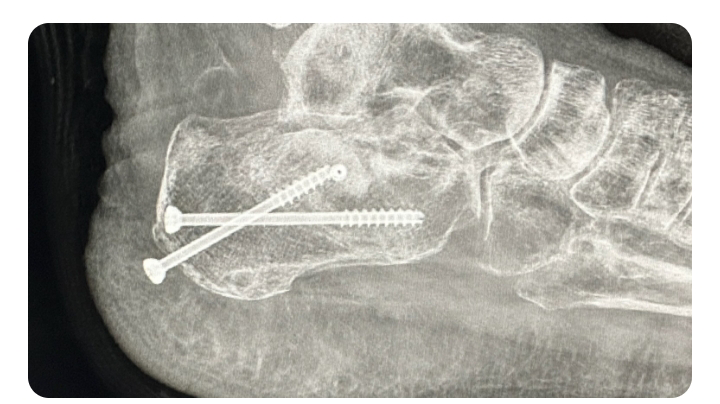

she's been working hard all her life but unfortunately a year and a half she had this unfortunately accident that she broke her heel bone in pieces she was ready to buy her dream house right before this accident happened now she spent all her savings in this situation and now she needs another surgery because the screws are coming out and she can potentially get the bone infected and high risk to get her foot amputate . . she cannot get social security and not disability because she worked with 1099 .. she needs help to keep up with rent and bills and she's terrified to get evicted most because she have two puppies that she needs to protect , and Plus she's been dealing with depression , she's in a good attitude and hope , from my heart thank you. Alma